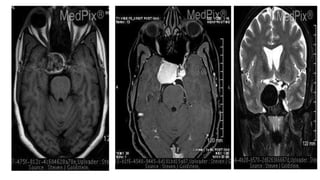

MRI

40 year old woman presents to the Eye Clinic

with a new onset of "double vision“

Right Sixth Cranial Nerve Palsy (Abducen

palsy)

Axial

MR - T2 weighted

There is a giant (>25mm) aneurysm in the

right cavernous sinus. There is another,

smaller ICA aneurysm in the left cavernous

sinus. The eyes show dysconjugate gaze, with

the right eye unable to move laterally - an

abducens (6th) nerve palsy.

DWI

MRI 40 year oldwoman presents to the Eye Clinic with a new onset of "double vision“ Right Sixth Cranial Nerve Palsy (Abducen palsy) Axial MR - T2 weighted There is a giant (>25mm) aneurysm in the right cavernous sinus. There is another, smaller ICA aneurysm in the left cavernous sinus. The eyes show dysconjugate gaze, with the right eye unable to move laterally - an abducens (6th) nerve palsy.